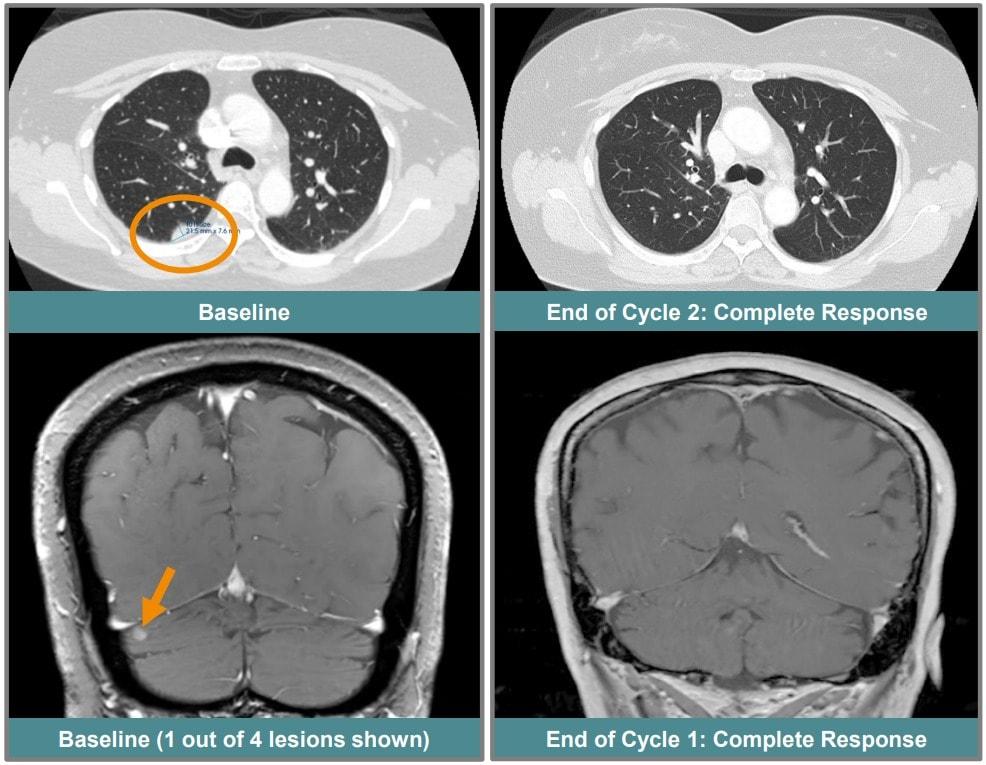

본문 이미지 - 지난해 유럽종양학회(ESMO)에서 발표된 ORCI-114 완전관해 환자 케이스.(ESMO 제공)/뉴스1 ⓒ News1

지난해 유럽종양학회(ESMO)에서 발표된 ORCI-114 완전관해 환자 케이스.(ESMO 제공)/뉴스1 ⓒ News1